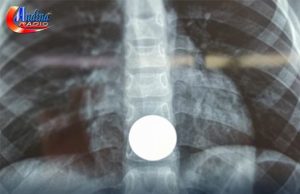

CHOTA: MEDICOS EXTRAEN MONEDA DE UN SOL QUE ATRAGANTO UN NIÑO...

El Hospital José H. Soto Cadenillas de Chota, en la región Cajamarca, logró una intervención médica crucial, al salvar la vida de un menor...